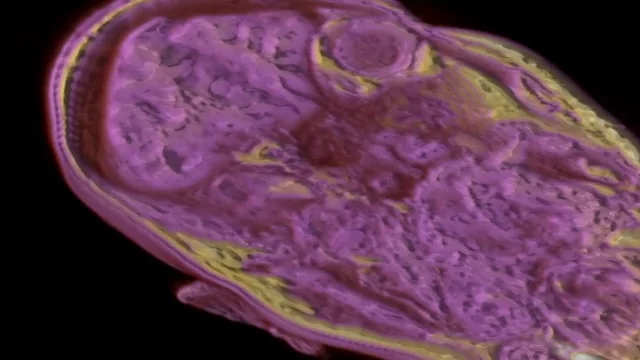

Marilène Oliver has worked with radiology and computer science researchers at the University of Alberta to create a series of high-resolution full body magnetic resonance (MR) scan datasets in order to create two new art installations for the Dyscorpia exhibition, both including virtual reality components. Based on the premise that the way we see ourselves informs how we understand ourselves, creating material and immaterial visions of the body based on data captured by a digitally mechanised machine offers an opportunity to compare and contrast the affectiveness of virtual and real media. Each work has an especially created audio created by Gary James Joynes using recordings from the original MR scan.

In Deep Connection a single body floats prone in virtual reality space. The viewer can walk around her and dive inside her body. Her hand is outstretched, waiting for a human connection. Space Invaders creates an uncanny experience of having our personal physical space invaded by virtual bodies. Both virtual reality works are experienced as parts of multimedia installations that include sculptural elements that have been created from the same MR data used to render the virtual reality bodies.